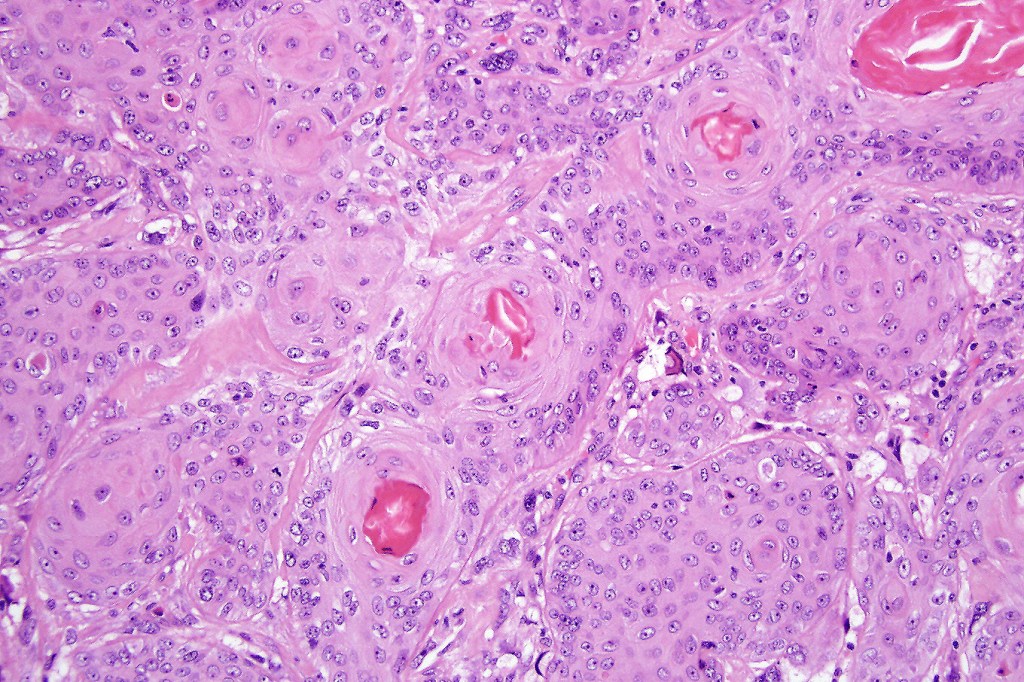

Carcinosarcoma

Cutaneous carcinosarcoma (metaplastic carcinoma, carcinoma with heterologous differentiation)

Histological features

•Osteoid

•Chondroid

•Smooth muscle

•MFH-like features with osteoclasts

•Neural differentiation